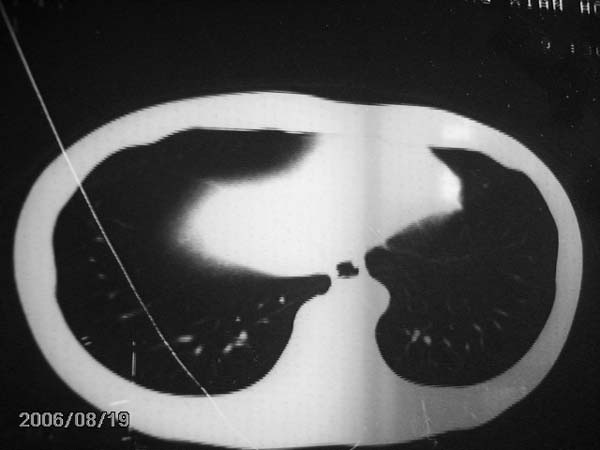

男,13岁,发烧半月,干咳无痰,正规使用抗生素半月,现在仍是午后低烧!!!未做痰检

右肺结核,右肺中叶不张

右肺中叶大片状密度增高影,内密度不均匀,右肺门处增大,应该是淋巴结肿大,结合临床首先考虑原发性肺结合可能性大,不排除合并感染可能,建议治疗后复查.

灶内密度不均,似乎有囊状,条状影,考虑右中叶综合症; 从照片中看不出有无钙化灶,若明显则考虑结核性。

考虑中叶综合征(右肺门肿大淋巴结伴中叶阻塞性炎症)